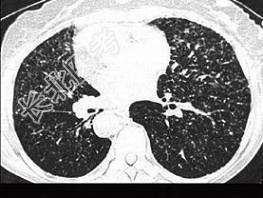

- 单项选择题女,23岁, 消瘦盗汗1月余,干咳1周, 偶痰中带血,影像如图, 最可能的诊断为 ( )

A、粟粒性肺结核

B、含铁血黄素沉着

C、弥漫性肺纤维化

D、慢性支气管炎

E、SLE肺部侵犯